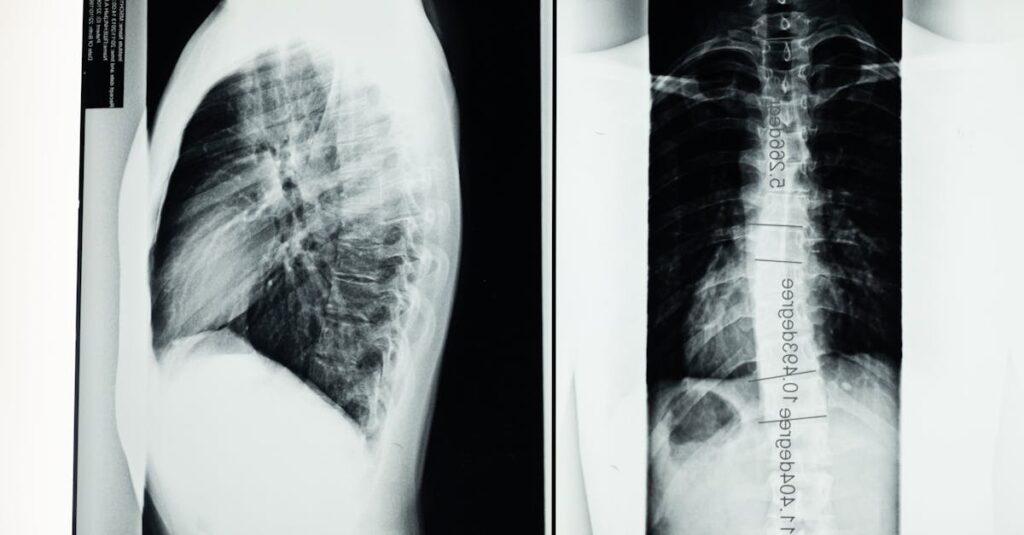

Quels examens permettent de diagnostiquer une hernie discale?

Une IRM ou une radiographie est utilisée pour confirmer le diagnostic d’une hernie discale.